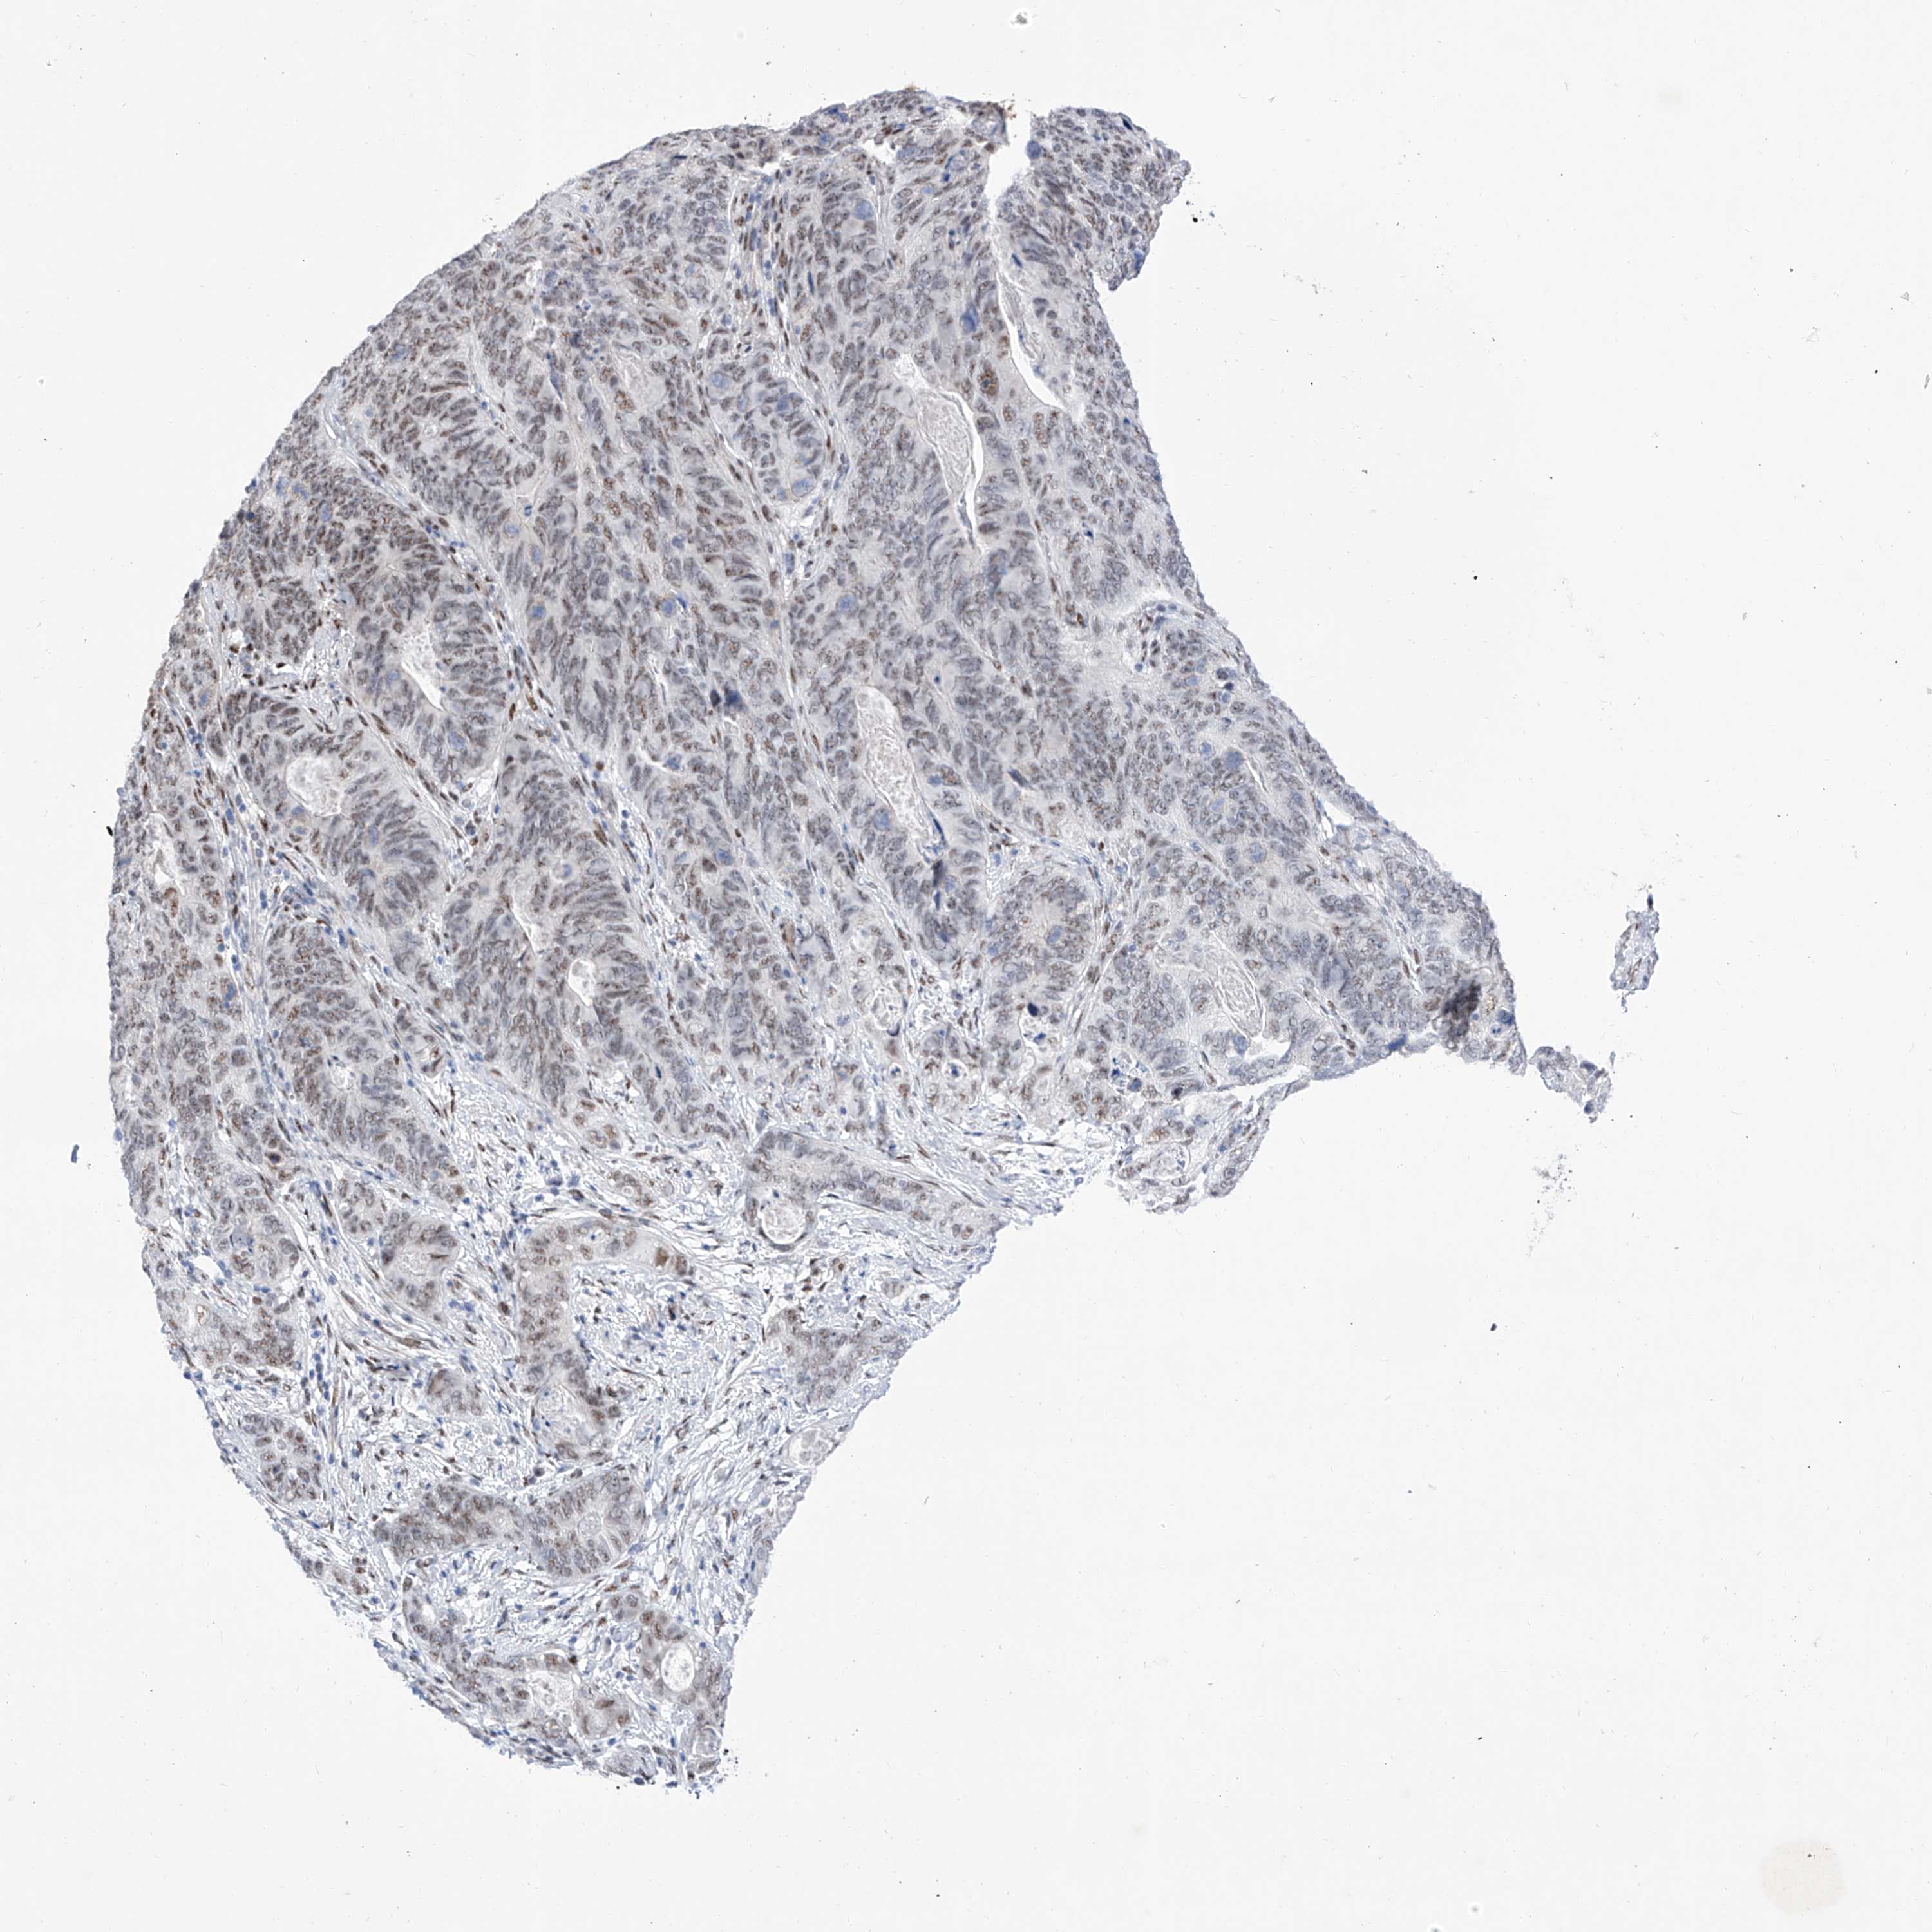

STOMACH CANCER - Protein expressioni

A mouse-over function shows sample information and annotation data. Click on an image to view it in a full screen mode. Samples can be filtered based on level of antibody staining by selecting one or several of the following categories: high, medium, low and not detected. The assay and annotation is described here.

Note that samples used for immunohistochemistry by the Human Protein Atlas do not correspond to samples in the TCGA dataset.

Antibody stainingi

Antibody staining in the annotated cell types in the current human tissue is reported as not detected, low, medium, or high, based on conventional immunohistochemistry profiling in selected tissues. This score is based on the combination of the staining intensity and fraction of stained cells.

Each image is clickable and will lead to virtual microscopy that enables deeper exploration of all samples and also displays staining intensity scores, fraction scores and subcellular localization as well as patient and tissue information for each sample.

Antibody HPA031619

Staining

High

Medium

Low

Not detected

Intensity

Strong

Moderate

Weak

Negative

Quantity

>75%

75%-25%

<25%

None

Location

Nuclear

Cytoplasmic/membranous

Cytoplasmic/membranous,nuclear

Adenocarcinoma, NOS